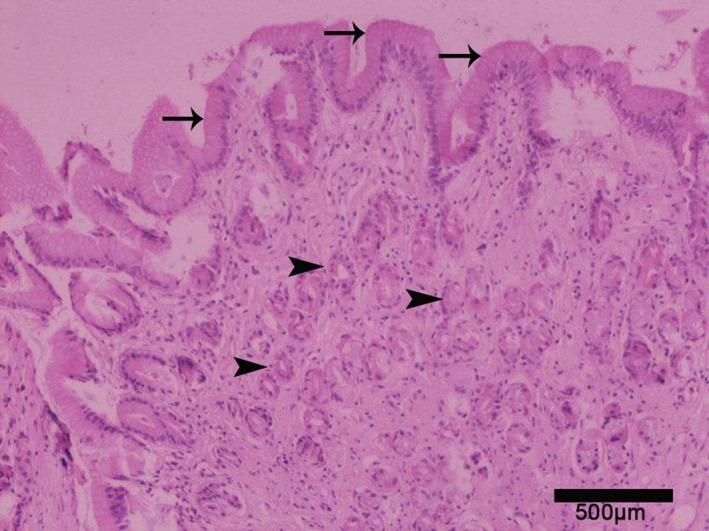

The majority of cats with clinical signs of FCG exhibited some degree of esophagitis especially in the proximal (44/58) and distal (53/58) parts (P < 0.001) with or without columnar metaplasia, compared to controls. All cats lacked signs related to gastrointestinal disease. Salivary and esophageal lumen pH were not statistically different compared to controls.

与对照组相比,大多数有FCG临床症状的猫表现出一定程度的食管炎,尤其是在近端(44/58)和远端(53/58)部分(P<0.001),有或无柱状化生。所有猫均无胃肠道疾病相关体征。与对照组相比,唾液和食管腔pH值无统计学差异。